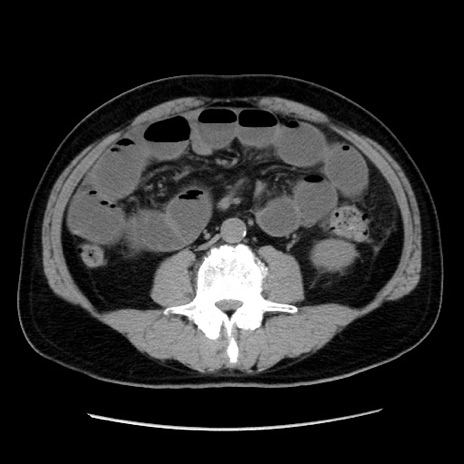

冠状断像

症例16(横断像)

【症例】 70歳代男性

【主訴】 腹痛、嘔吐

【現病歴】 約1ヶ月前より間欠的に腹痛と嘔吐あり、当院消化器内科を受診したところCTで多発する肝臓のLDAを指摘され、精査中であった。以降は消化器症状は安定していたが、2日前より嘔気と腹痛があり、同日より排便・排ガスが消失した。改善認めず、 本日、救急外来を受診した。

【既往歴】 大腸ポリープ切除後。

【身体所見】意識清明・会話良好、BT 36.3℃、BP 127/80mmHg、 P 80bpm、腹部:膨満あり、平坦・軟、上腹部正中および下腹部正中に圧痛あり、反跳痛なし、筋性防御なし。

【データ】WBC 7200、CRP 0.77